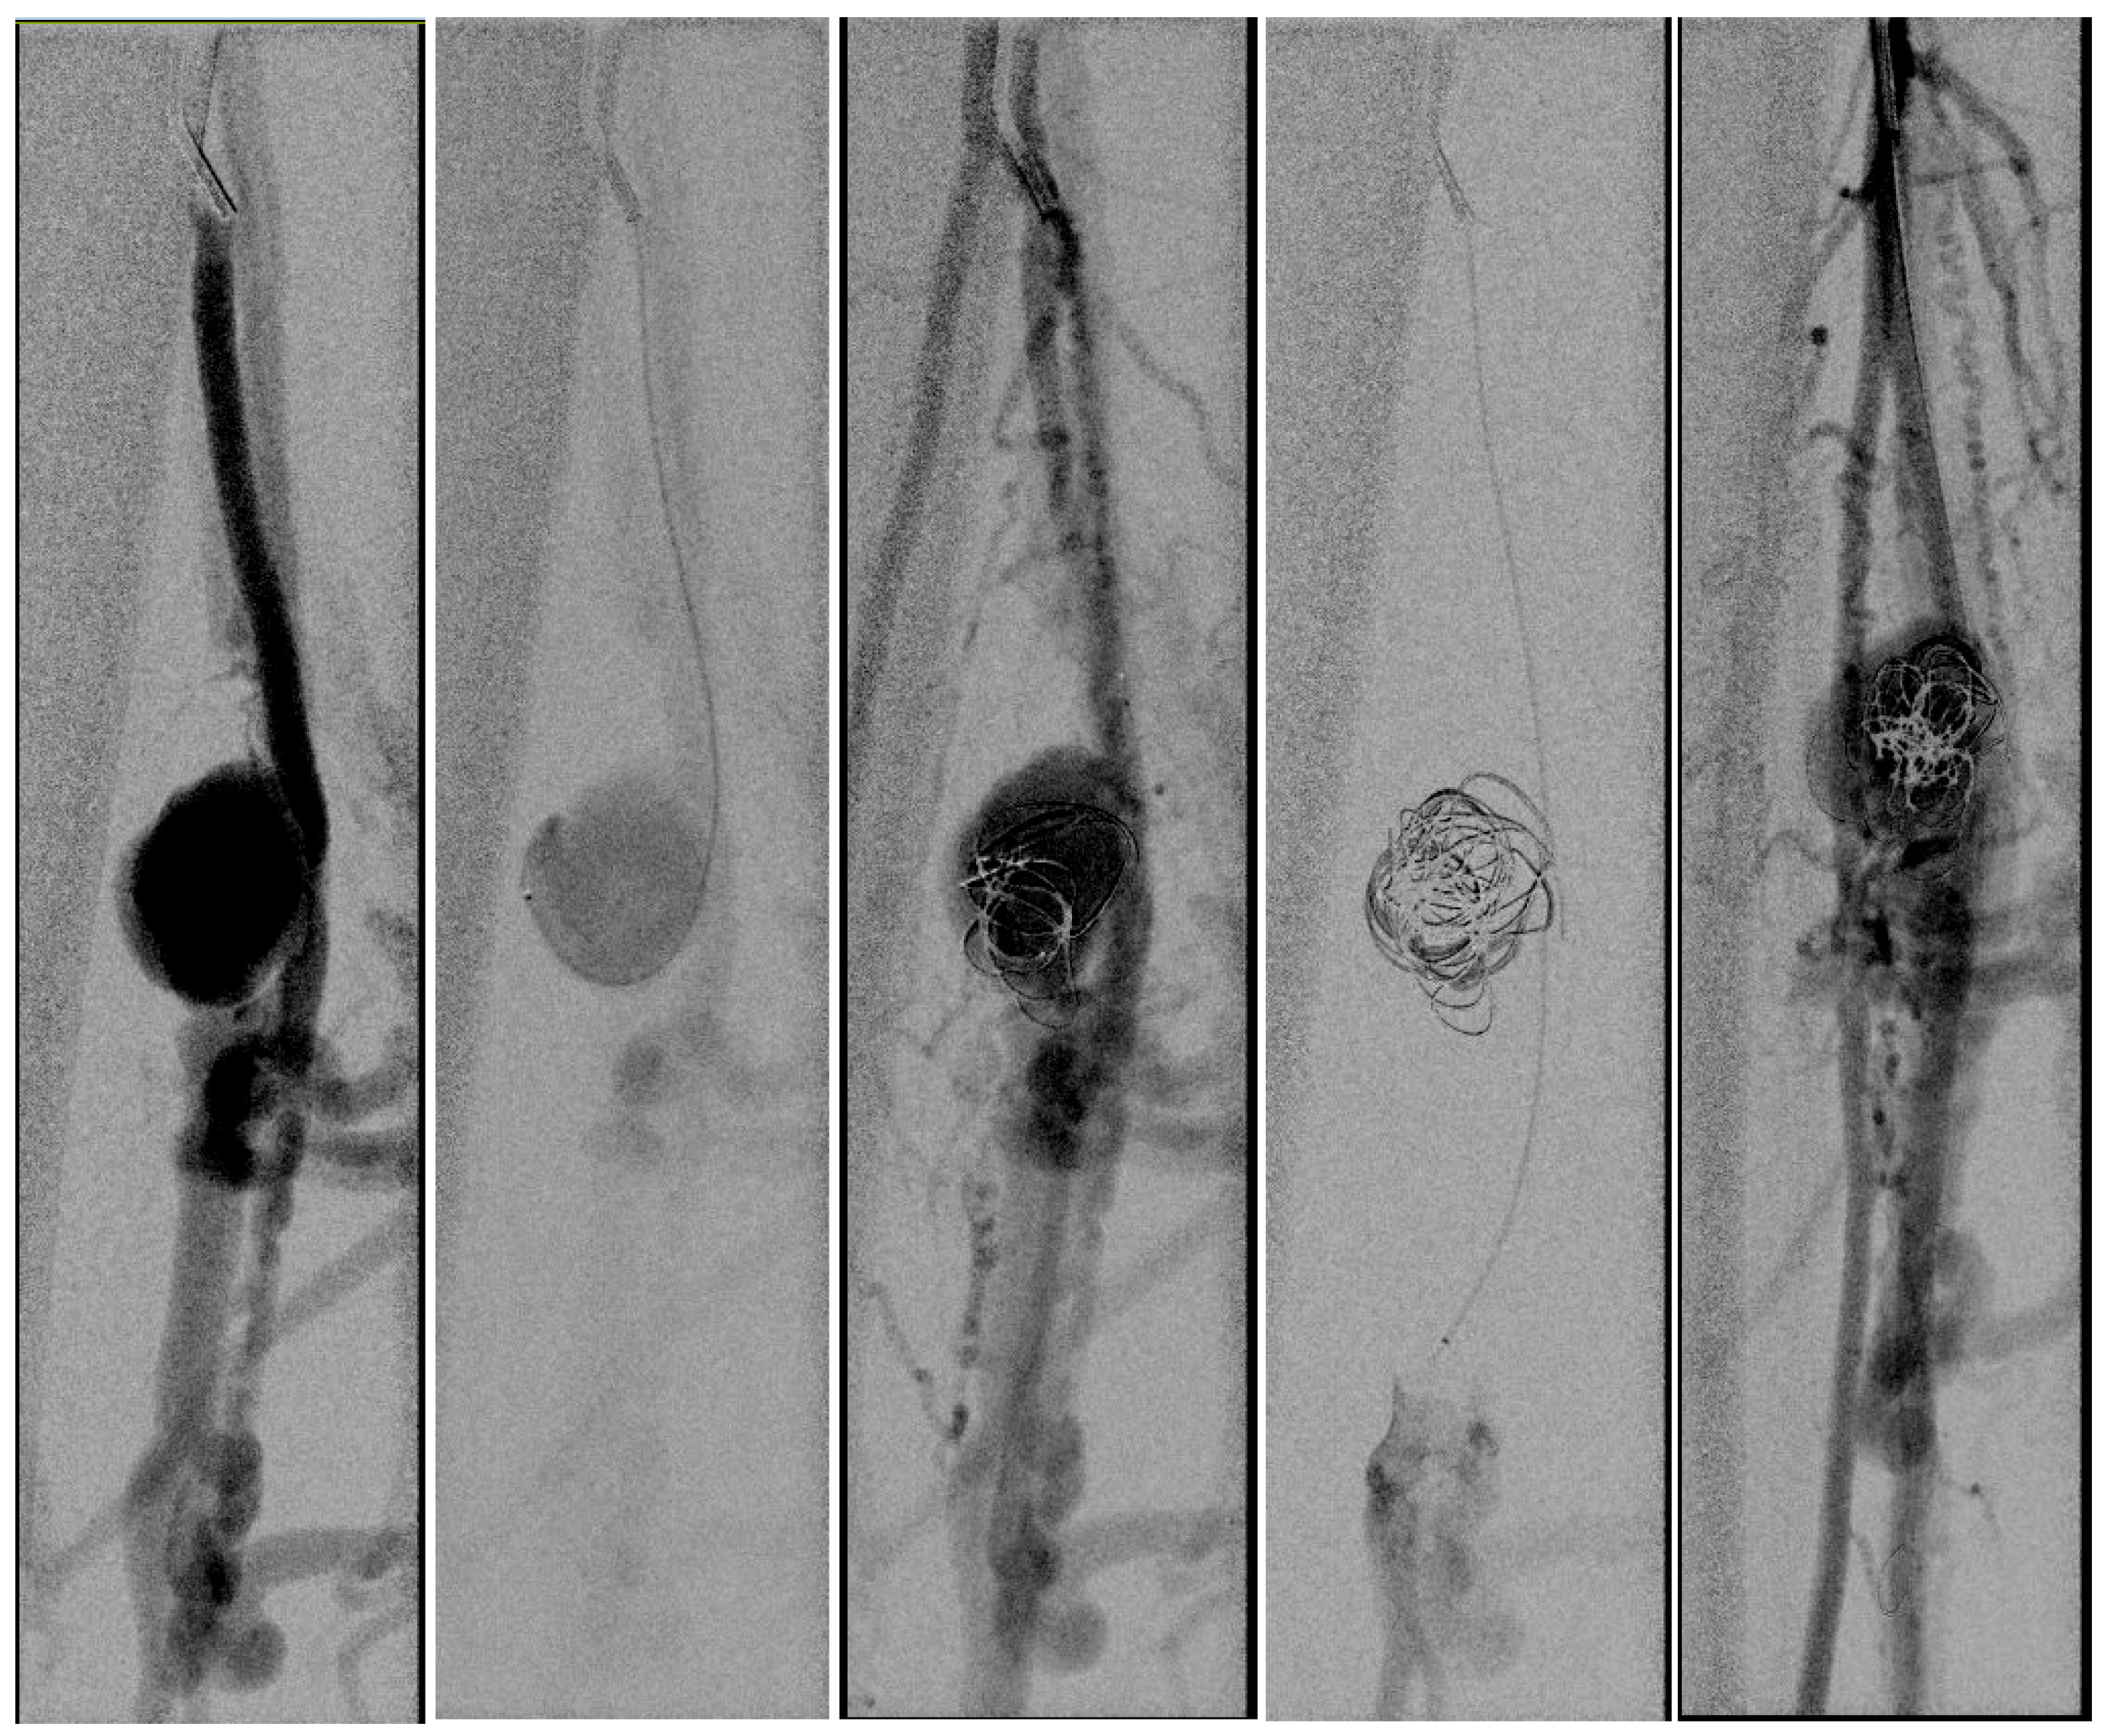

- Yamamoto Y. Et al. Endovascular coil embolization of a large tibioperoneal trunk pseudoaneurysm. Journal of Vascular Surgery Cases and Innovative Techniques 2020; Volume 6 number 3.

- Micari, A. et al. Tibioperoneal trunk pseudoaneurysm coil embolization 2010 Catheter Cardiovasc Interv vol.75 (2) 276-8.

- Miura, T. et al. Iatrogenic peroneal artery pseudoaneurysm treated by transluminal coil embolization 2013 Cardiovasc Interv Ther vol. 28 (1) 128-30.